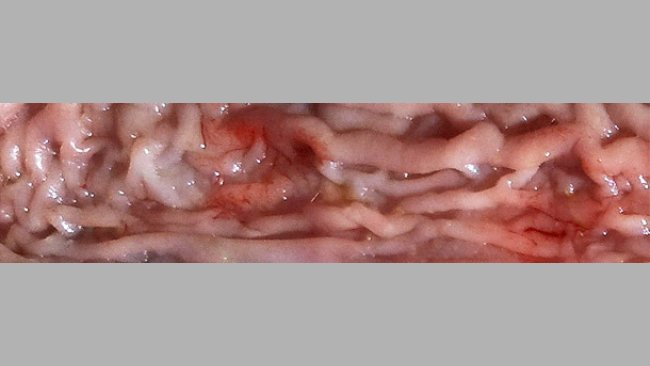

Dyzenteria świń, starzy nowi wrogowie

Choroby układu pokarmowego świń, które wcześniej były traktowane indywidualnie, ukierunkowane na pojedynczy patogen, obecnie tworzą zespół chorób układu pokarmowego, z którym musimy zmierzyć się z różnych perspektyw.